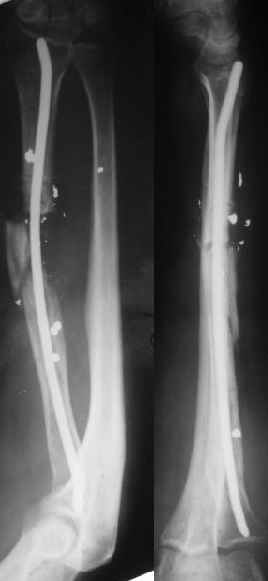

Alexander Chelnokov 22 Март 2004, 19:45

2

В приложении - снимок по окончании дистракции, и после смены аппарата на стержень (довольно толстый, 5 мм). С входом в канал на центральном отломке пришлось малость попотеть, промежуточный отломок его прикрывал. Но все-таки удалось закрыто проколупать. Надеюсь, дня через 3-4 после операции можно будет передать пациента нейрохирургам. Буду признателен за критику и комментарии.

Все за и про интрамедуллярной фиксации этого перелома луча уже обсуждались - все идет по плану.

Твоя концепция стабилизации отломков, своего рода *протезирования* лучевой кости продемонстрирована на Ргграммах. Прямого кость-кость контакта между дистальным и промежуточным фрагментами не получилось, что может скомпрометировать сращение перелома, хотя при первично стабильной фиксации и сохраненной надкостнице можно рассчитывать не

формирование периостальной мозоли (видимо этот механизм и работал в твоих прежних случаях).

Осталось дело за нейрохирургами и физиотерапевтами.